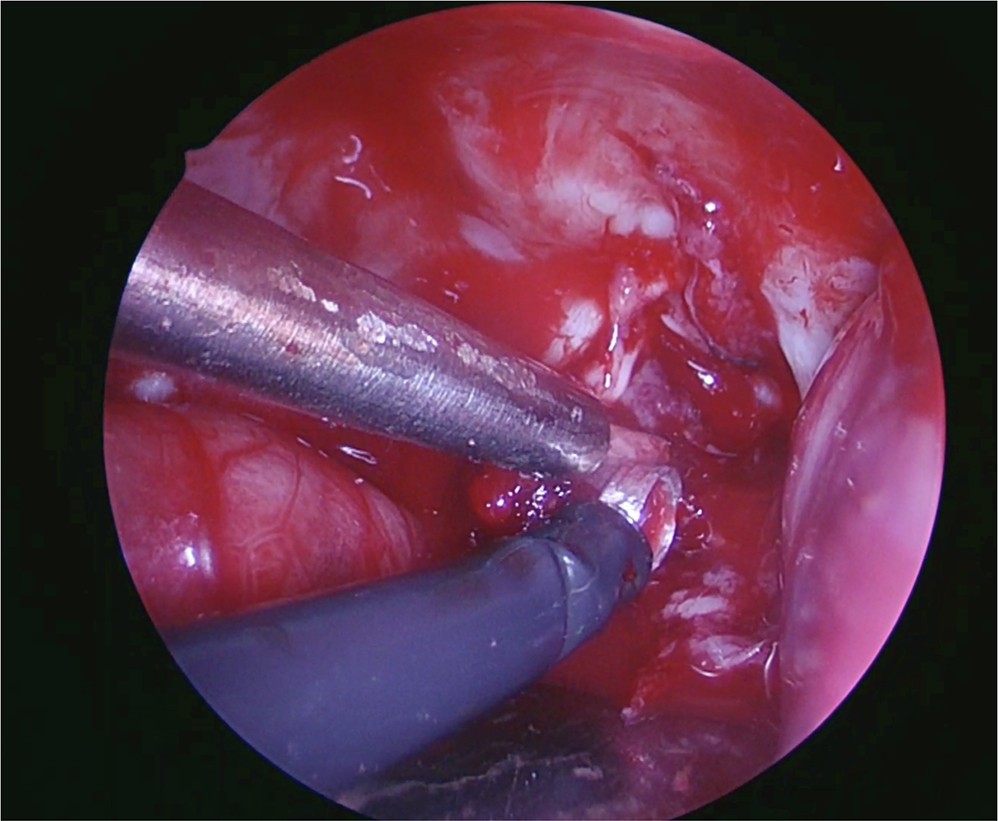

Curette in the supracerebellar approach.